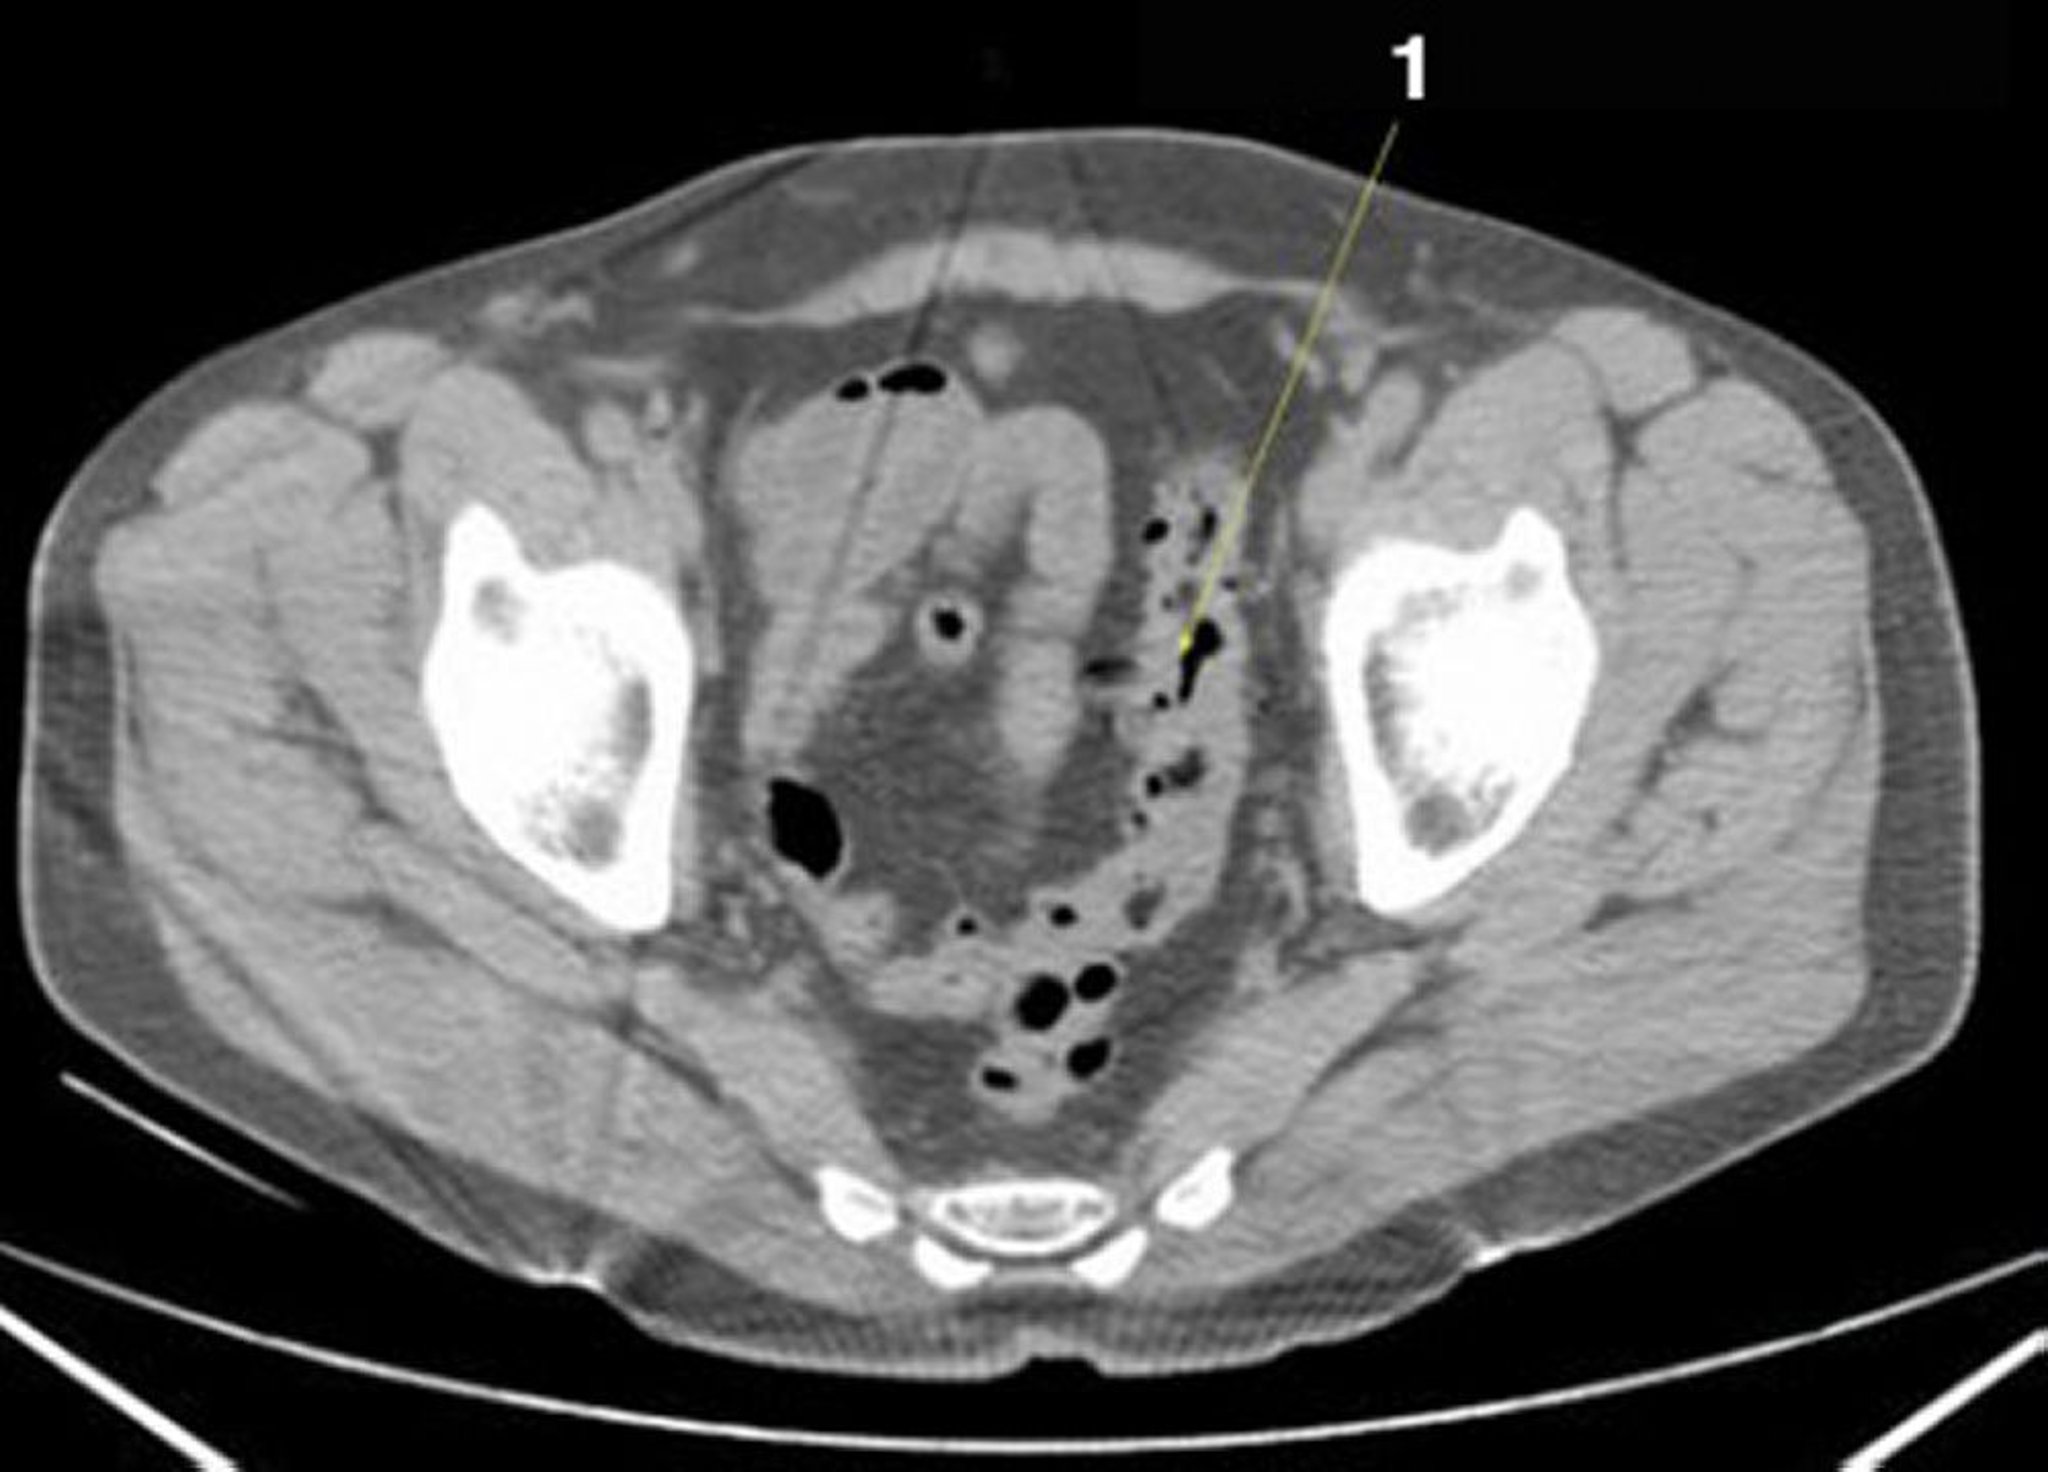

Tomografía computarizada sin contraste de abdomen y pelvis que muestra anatomía normal (corte 25)

1 = colon sigmoideo.